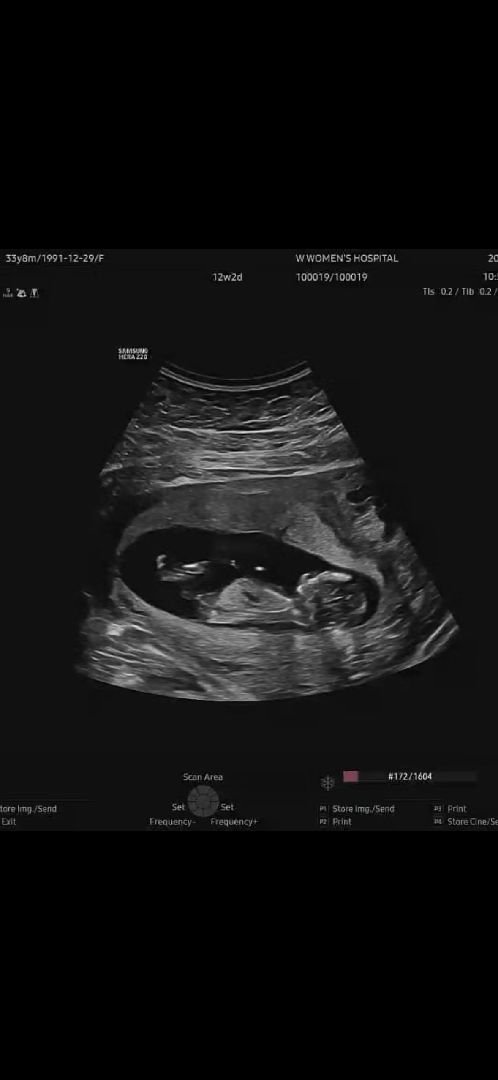

12주차 성별뭘까요~?

궁금하네여 ㅎㅎ